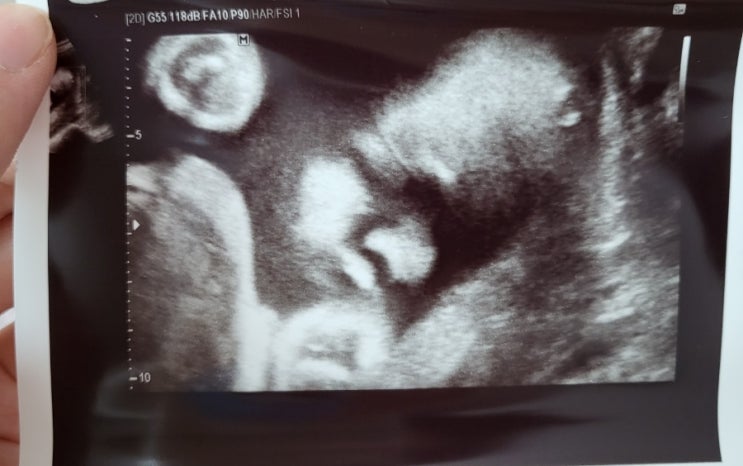

임신 이야기 :) 범계 봄빛병원 임신 30주차 초음파, 태동

안녕하세요 임신 30주차 망고어멈이에요 추석은 잘 보내셨나요? 추석당일 시댁에서 집으로 돌아오는 길 석...

망고 이야기 :) 임신 27주차 범계 봄빛병원 입체초음파, 백일해 접종

안녕하세요 매일매일 자고 일어날 때마다 우리 망고 쑥쑥 클 생각에 기쁜 망고어멈이에요 오늘로 딱! 임신 ...